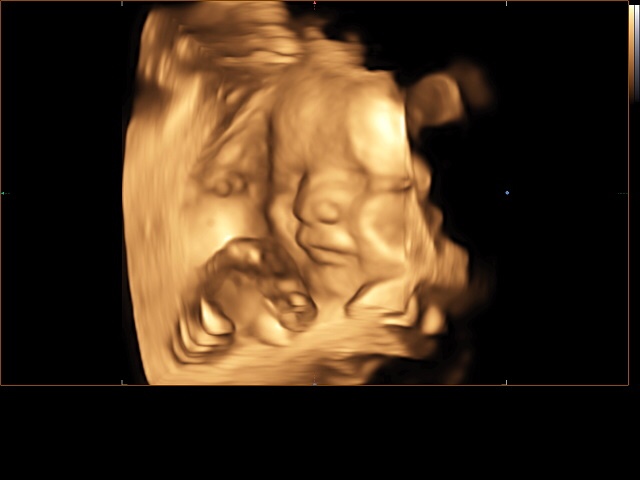

А вот и наш третий скрининг)))) все в норме! По весу 1800. Врач сказала хороший щекастый мальчик с большой морковкой 😂😂😂😂

Делали 4д с записью на диск видио и фото